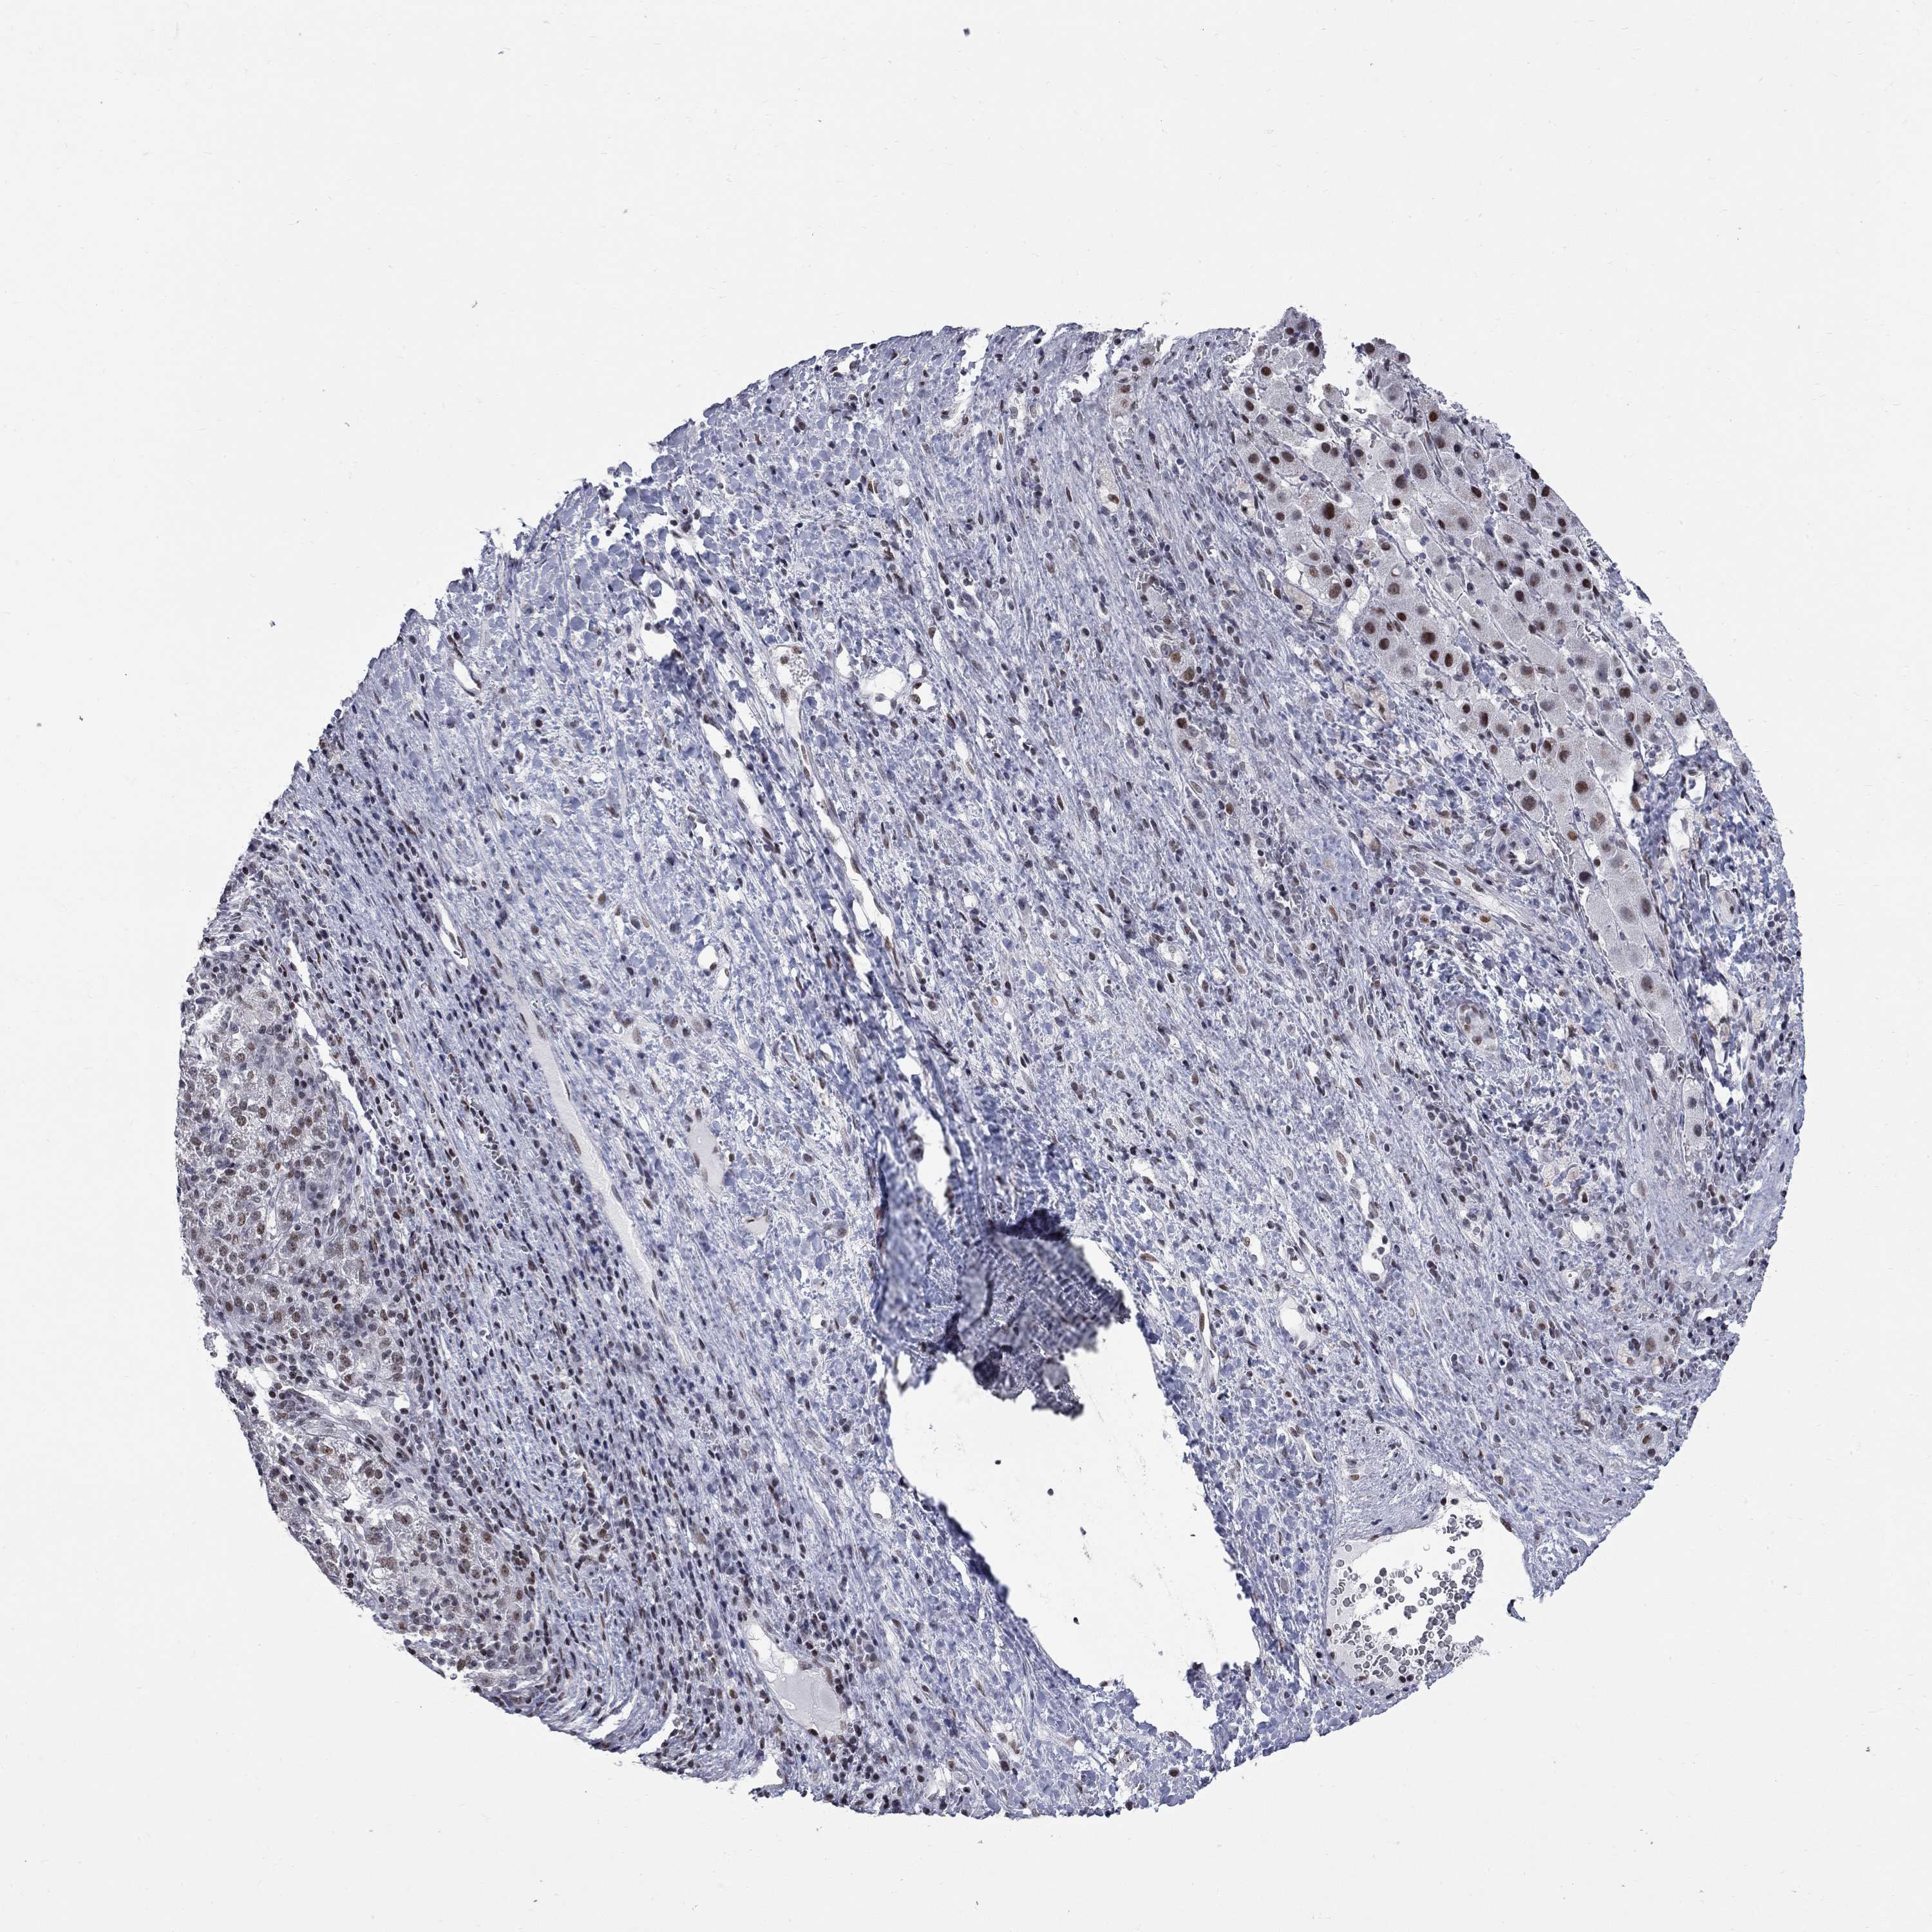

LIVER CANCER - Protein expressioni

A mouse-over function shows sample information and annotation data. Click on an image to view it in a full screen mode. Samples can be filtered based on level of antibody staining by selecting one or several of the following categories: high, medium, low and not detected. The assay and annotation is described here.

Note that samples used for immunohistochemistry by the Human Protein Atlas do not correspond to samples in the TCGA dataset.

Antibody stainingi

Antibody staining in the annotated cell types in the current human tissue is reported as not detected, low, medium, or high, based on conventional immunohistochemistry profiling in selected tissues. This score is based on the combination of the staining intensity and fraction of stained cells.

Each image is clickable and will lead to virtual microscopy that enables deeper exploration of all samples and also displays staining intensity scores, fraction scores and subcellular localization as well as patient and tissue information for each sample.

Antibody HPA076284

Staining

High

Medium

Low

Not detected

Intensity

Strong

Moderate

Weak

Negative

Quantity

>75%

75%-25%

<25%

None

Location

Nuclear

Cytoplasmic/membranous

Cytoplasmic/membranous,nuclear

Carcinoma, Hepatocellular, NOS